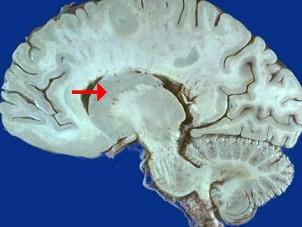

如图箭头所示为大脑哪个部位 ( )A、松果体B、中脑导水管C、豆状核D、尾状核E、丘脑

问题 如图箭头所示为大脑哪个部位 ( )

选项 A、松果体 B、中脑导水管 C、豆状核 D、尾状核 E、丘脑

答案 D